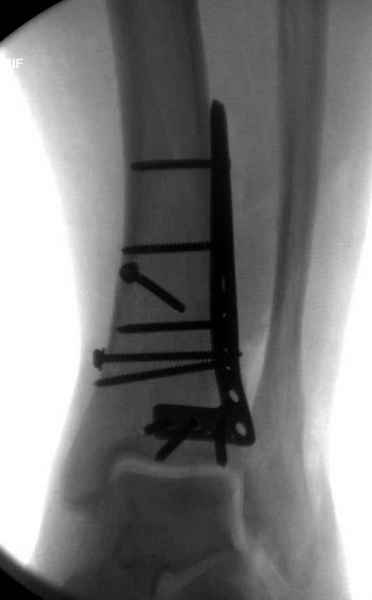

Публикации за последние пять лет показывают, что в лечении переломов пилона важным является состояние

мягких тканей. Поэтому при лечении пилона, особенно после высокоэнергетической травмы, необходимо придерживаться правила - лучше проводить запоздалую фиксацию, чем после операции иметь проблемы с мягкоткаными осложнениями.

После ExFix проведение компьютерной томографии считаем обязательным, получаем информацию о расположении крупных фрагментов, которая подскажет сторону операционного доступа и направления проведения фиксирующего материала.

Фиксация наружной лодыжки подсказывается переломом, а малоберцовая является ключом-ориентиром для длины конечности.

В данном случае ориентир сохранен, малоберцовая хорошо сочленена с тараном. Но несмотря на отсутствия перелома на снимке, все-таки для страховки можно было бы сделать снимок проксимальной части конечности.

Любая фиксация - преконтурированные пластины с уголовой стабильностью, медиальная, латеральная в зависимости от нахождения отломков или наружная фиксация типа аппарата Илизарова подходят для ранней мобилизации.

Не все переломы пилона фиксируются медиальной

пластиной, поэтому, учитывая что большой фрагмент

находится на латеральной стороне, я бы применил

передне-латеральную пластину.